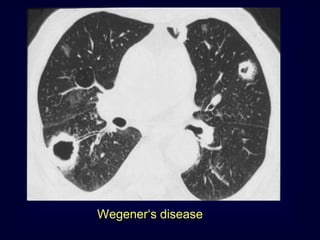

Wegener„s disease

Rheumatoid Arthritis